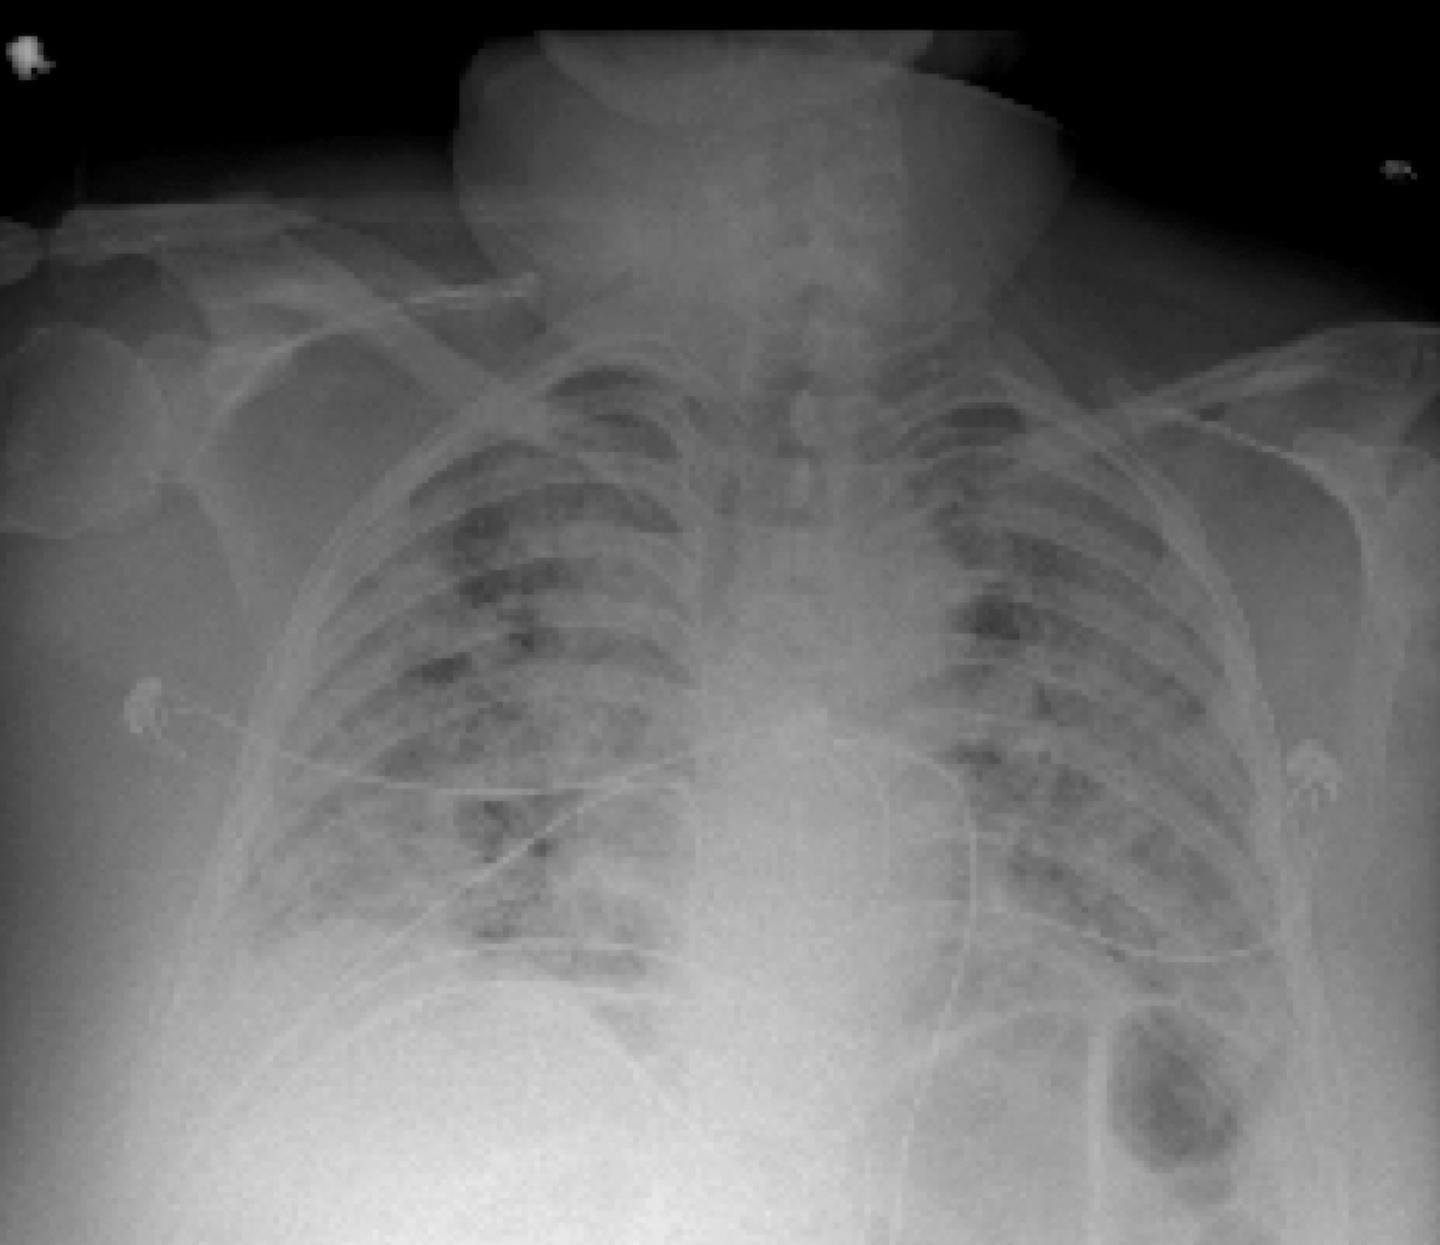

This photo gallery shows the variety of radiological presentations of COVID-19 (SARS-CoV-2) in medical imaging, including computed tomography (CT), radiograph X-rays, ultrasound, echocardiograms and magnetic resonance imaging (MRI). The radiology images show examples of typical COVID pneumonia in the lungs and the numerous complications the virus causes in the body in multiple organs, including the brain, kidneys, heart, abdomen and vascular system.

Ultrasound, especially hand-held ultrasound imaging devices, have become a primary imaging modality for novel coronavirus because of the ease to bag the device and sterilize it after use. CT and mobile X-ray systems are also used as front-line imaging systems for COVID-positive or suspected COVID patients.